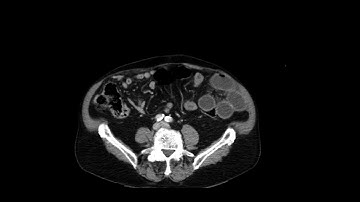

Abdominal CT Tutorials - Small bowel obstruction